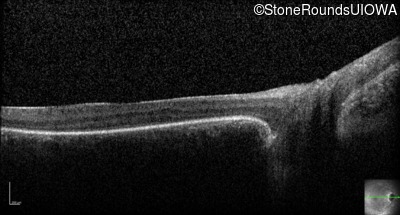

Optical Coherence Tomography - Left - Light Perception

Exemplar